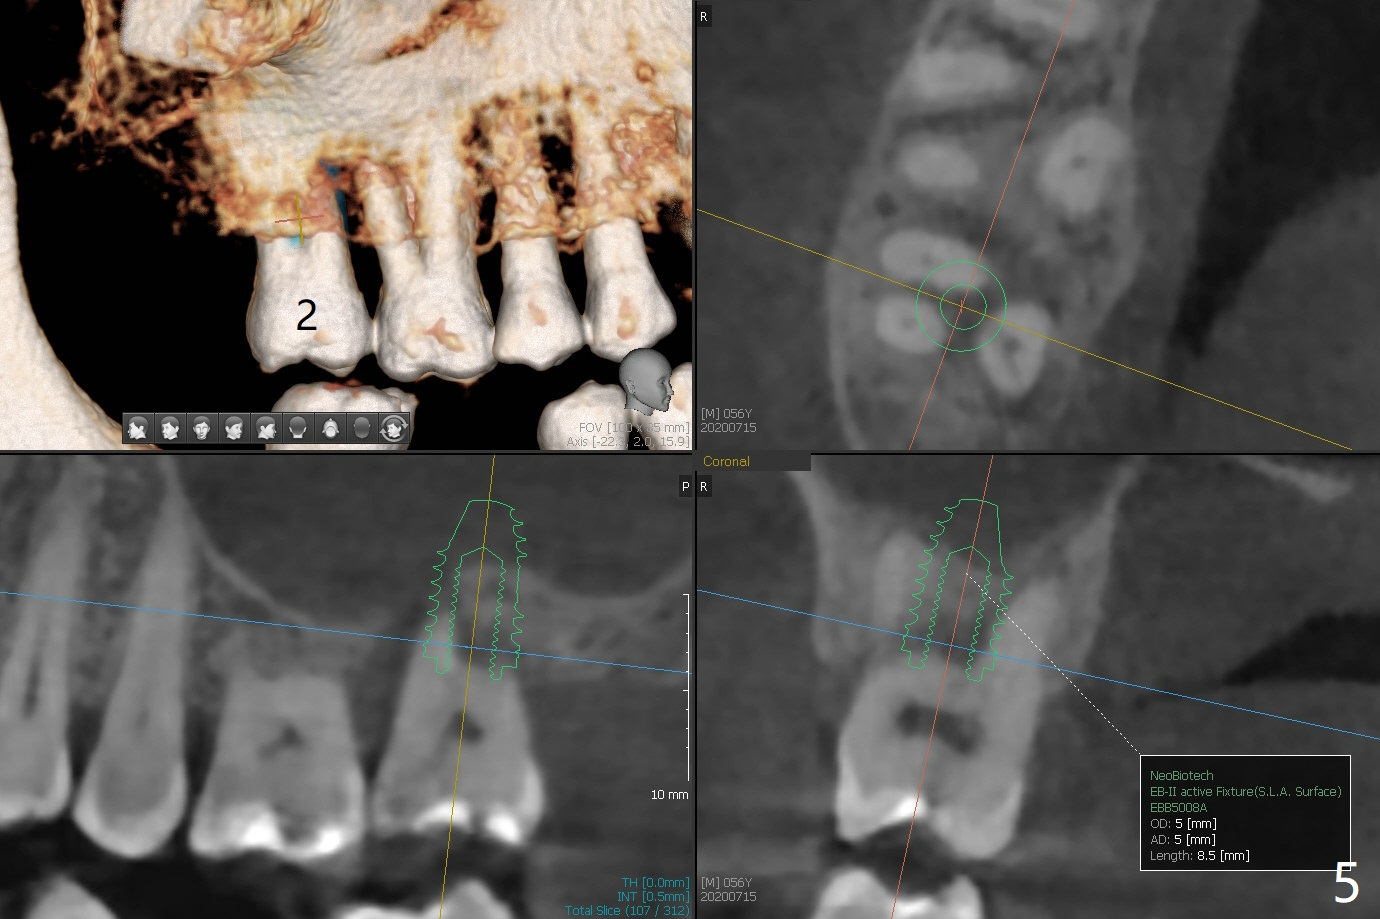

A 56-year-old man (smoker) has pain at #2 (Fig.1-3 thickened sinus membrane (R>L), C: mucous retention cyst) associated with subgingival crack (Fig.4 arrowheads). A 5x8.5 mm implant will be immediately placed with sinus lift aided by PRF membrane (Fig.5). A narrow implant will be placed at #30 (Fig.6).